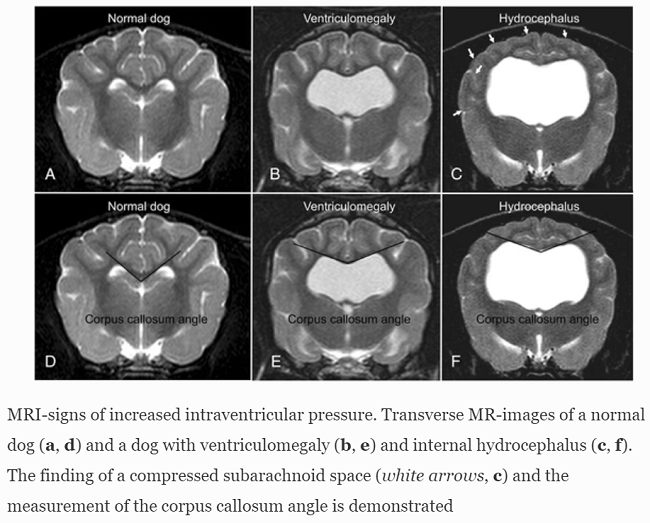

More advanced imaging, computed tomography (CT) and especially magnetic resonance imaging (MRI), is necessary to fully determine the extent of the ventriculomegaly or hydrocephalus, to identify obstructive lesions, and to rule out other disorders. MRI is more sensitive than CT in diagnosing these disorders. However, CT is useful for follow-up of previously diagnosed patients. (See below, the MRI images comparing normal dogs with dogs diagnosed with ventriculomegaly and hydrocephalus. From Laubner 2015.)

Magnetic resonance imaging signs of high intraventricular pressure - comparison of findings in dogs with clinically relevant internal hydrocephalus and asymptomatic dogs with ventriculomegaly. Steffi Laubner, Nele Ondreka, Klaus Failing, Martin Kramer, Martin J. Schmidt. BMC Vet. Res. August 2015; doi: 10.1186/s12917-015-0479-5. Quote: Background: Magnetic resonance imaging (MRI) findings of canine brains with enlarged ventricles in asymptomatic dogs were compared to those in dogs with clinically relevant internal hydrocephalus, in order to determine the imaging findings indicative of a relevant increase in intraventricular pressure. Discrimination between clinically relevant hydrocephalus and ventriculomegaly based on MRI findings has not been established yet and is anything but trivial because of the wide variation in ventricular size in different dog breeds and individuals. The MRI scans of the brains of 67 dogs of various breeds, skull conformation and weight were reviewed retrospectively. Based on clinical and imaging findings, the dogs were divided into three groups: a normal group (n=20), a group with clinically silent ventriculomegaly (n=25) [including 4 cavalier King Charles spaniels] and a group with severe clinically relevant internal hydrocephalus (n=22) [including 1 CKCS]. In addition to the ventricle/brain-index, a number of potential subjective signs of increased intraventricular pressure were recorded and compared between the groups. Results: The ventricle/brain-index was significantly higher in dogs with relevant hydrocephalus and a threshold value of 0.6 was specified as a discriminator between internal hydrocephalus and ventriculomegaly. Other MR imaging findings associated with clinically relevant hydrocephalus were an elevation of the corpus callosum, dorsoventral flattening of the interthalamic adhesion, periventricular edema, dilation of the olfactory recesses, thinning of the cortical sulci and/or the subarachnoid space and disruption of the internal capsule adjacent to the caudate nucleus. Conclusion: A combination of the abovementioned criteria may support a diagnosis of hydrocephalus that requires treatment.